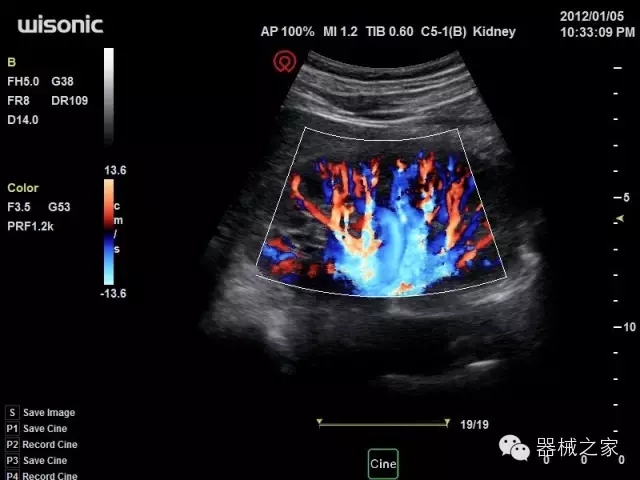

臨床圖片賞析

產(chǎn)品特點(diǎn)

·全球目前唯一一款配備主機(jī)雙探頭接口,整機(jī)重量(含電池)在5公斤以內(nèi)的便攜式彩超;

·一款互聯(lián)網(wǎng)彩超,只要有手機(jī)信號的地方就可以非常方便地實(shí)現(xiàn)遠(yuǎn)程會(huì)診和病案調(diào)??;

·鎂鋁合金外殼,堅(jiān)固可靠耐用;

·獨(dú)有的HoloTM PW 實(shí)時(shí)3取樣門PW成像技術(shù),精確進(jìn)行血管診斷;

·一鍵優(yōu)化B、Color、PW,Auto Doppler自動(dòng)識別血管位置、偏轉(zhuǎn)角度等,提高工作效率;

·30°超廣角精細(xì)偏轉(zhuǎn)成像技術(shù),更優(yōu)異的頻譜圖像;

·W+智能搜索引擎,快速尋找圖像;

·SSD、USB3.0保障開機(jī)快,導(dǎo)出圖像更快,減少等待時(shí)間;

·WIFI、網(wǎng)口、3G,多重聯(lián)網(wǎng)方式,全天候保障云端備份,不再擔(dān)心圖像丟失;

CFDA注冊證編號

·粵械注準(zhǔn)201522231208